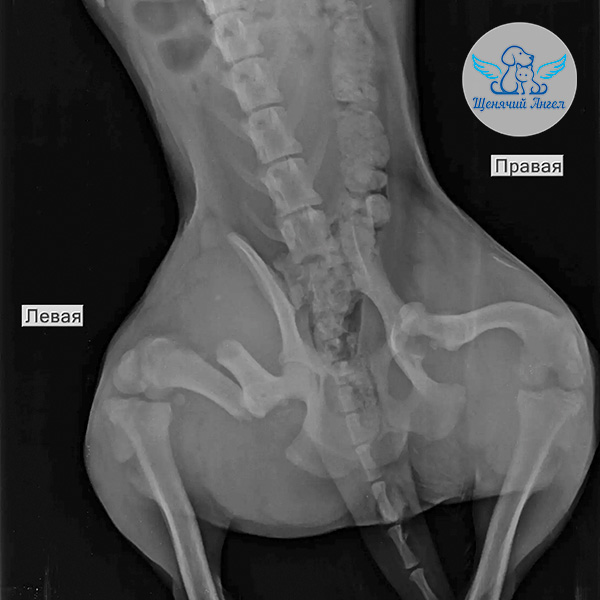

🙏🏻 Благодаря вашей помощи нам удалось забрать малышку и срочно доставить в местную ветеринарную клинику. Там Дуню обезболили и провели первичную диагностику. Рентген показал перелом левой задней лапы, также есть подозрение на перелом костей таза 🩻

Несколько дней Дуня находилась в стационаре – врачи стабилизировали её состояние и сняли острый болевой синдром. Как только транспортировка стала безопасной, мы перевезли Дуню в Москву, в клинику «Animal Vet», где сейчас она находится под круглосуточным наблюдением специалистов 🏥

По прибытии были взяты необходимые анализы на инфекционные заболевания 🦠. В ближайшие дни запланированы осмотр хирурга и повторный рентген – по их результатам будет определен план дальнейшего лечения и операции ❤️‍🩹